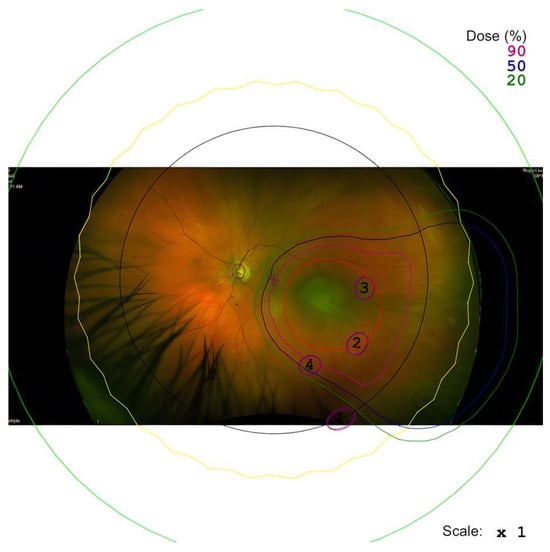

Outcomes Following Treatment with Notched Proton Beams for Peripapillary Choroidal Melanomas

Gulmeena Hussain, Jonathan Lam, Antonio Eleuteri, Linda Mortimer, Andrzej Kacperek, Bertil Damato, Heinrich Heimann and Rumana Hussain

Cancers 2025, 17(22), 3684; https://doi.org/10.3390/cancers17223684 - 18 Nov 2025

Purpose: Peripapillary choroidal melanoma provides a unique challenge; proximity to visually important structures, such as the optic disc and fovea, confers a high risk for the development of maculopathy and optic neuropathy, leading to poorer visual outcomes with most forms of radiotherapy. Ocular proton therapy (OPT) requires an aperture to shape the beam to the tumour. An aperture ‘notch’ may minimise damage to the optic disc and/or the fovea. This study aims to explore if there are any additional advantages to incorporating a notch over the optic nerve beam area. Design: Retrospective audit (cohort study). Participants: Participants included eighty-three patients treated at Liverpool with proton beam therapy from January 2012 to March 2020 for their peripapillary choroidal melanoma. All had a minimum of two and a half years of follow-up vision data; this was to ensure there was enough visual acuity assessment data to perform sufficient analysis. Patients excluded had choroidal melanoma situated over 3 mm from the optic disc, as these were unlikely to have an aperture notch. Methods: A retrospective audit was undertaken in accordance with the Declaration of Helsinki, and registered with the Royal Liverpool Hospitals audit department (audit reference number: Ophth/SE/2024-25/25). Data was collated from the Liverpool Ocular Oncology database, clinic letters and the individual proton beam 3D plans. Robust statistical analysis using a mixed effects model was used to explore associations between notched beams and vision loss and complications. Main Outcome Measures: The primary outcome measure is visual acuity loss post-proton beam therapy. Secondary outcome measures were enucleation and other complication rates. Results: Analysis shows that at 10 years post-OPT, there would be an expected 0.058 (p = 0.077) logMAR of vision saved using a notch for the optic disc compared to no notch (normal apertures); this is considered clinically significant. This cohort also loses vision at a slower rate than other cases. No other predictors were found to be statistically significant for loss of vision, and notched beams showed no advantage in reducing rates of complications. Conclusions: There is some evidence of a trend that utilising a notch for optic disc does show long-term vision benefit; it demonstrates a clinically significant benefit in patients with peripapillary choroidal melanoma.

(This article belongs to the Section Cancer Therapy)